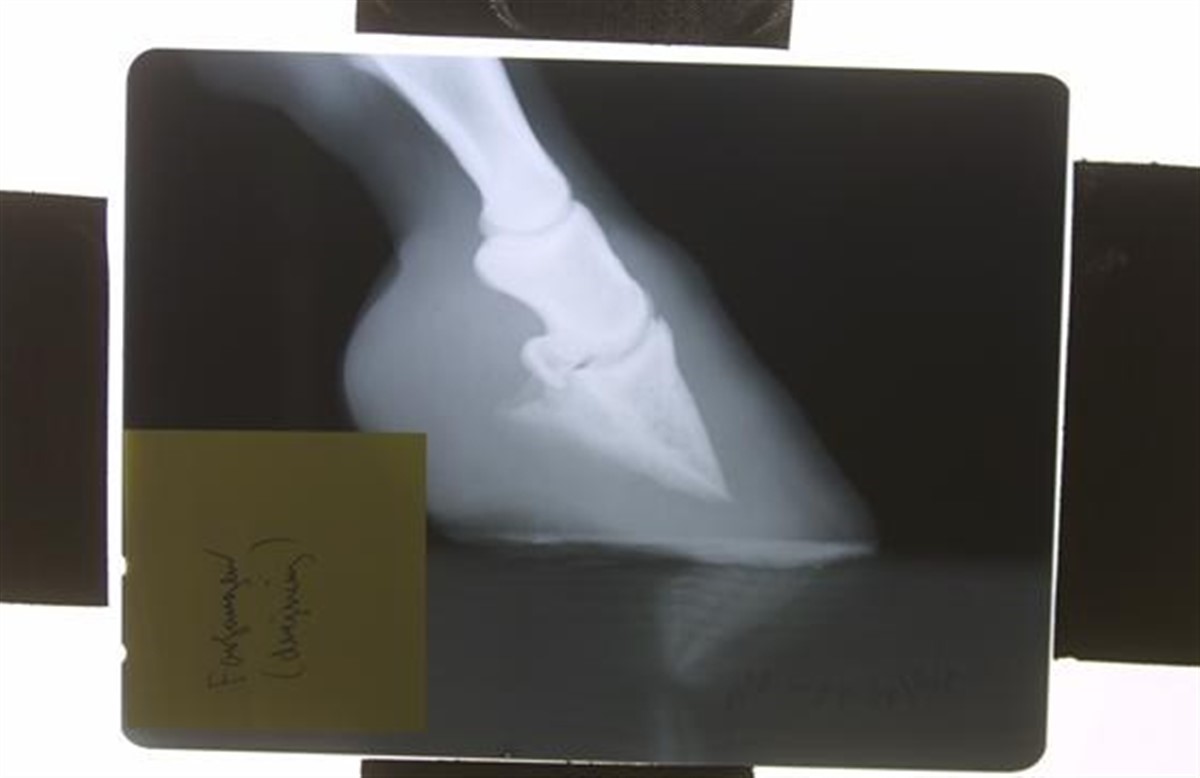

Australske forskere har gjort et gennembrud i forhold til forståelsen af, hvordan insulinvarianten af forfangenhed opstår

Doktor Melody de Laat og doktor Chris Pollitt fra Australian Equine Laminitis Research Unit ved University of Queensland har opdaget, at receptorer (særlige molekyler i cellernes overflade) designet til at modtage insulinlignende vækstfaktor 1 (IGF-1) kan være bindende til insulin i stedet, hos heste med et højt insulinniveau. Opdagelsen kan være med til at gøre forskere i stand til at udvikle metoder til at blokere IGF-1 receptorerne, så de ikke modtager insulin og dermed hindre sygdommen i at opstå. Samme receptorer har også vist sig at være skyld i metastaser for ondartede svulster hos mennesker, og der er derfor allerede gang i udviklingen af medicin, der kan blokere disse receptorer. Samme medicin kan også vise sig at være brugbar i behandlingen af heste der let kan udvikle forfangenhed gennem et for højt insulinniveau. Læs mere om forskningen i forfangenhed via linket til højre.